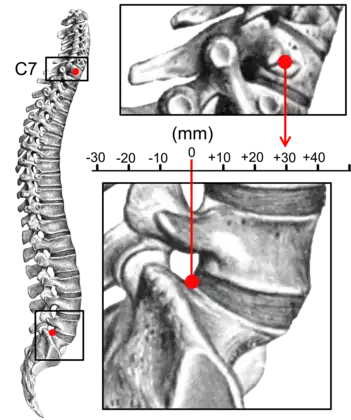

TK: Thoracic kyphosis- Measurements of spinopelvic parameters

Sagittal balance measurement.[7]

Kyphosis can be graded in severity by the Cobb angle. Also, sagittal balance can be measured. The sagittal balance is the horizontal distance between the center of C7 and the superior-posterior border of the endplate of S1 on a lateral radiograph.[7]